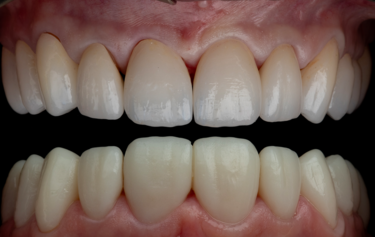

The patient returned after two weeks, and the final restorations were once again assessed. All margins, occlusion and excursions were re-checked and there were no further adjustments necessary (Fig. 24 & 25). Note the beautiful tooth morphology and the detailed surface texture that is achievable with modern digitally designed tooth libraries and state-of-the-art milling machines. The transfer of digital design to final restoration is an exact replication and this can be seen on the comparison of digital overlay against the final zirconia restorations in Figure 26

Figure 27: integration of final restorations at 2-week review versus initial presentation

By approaching multiple restorations in the same methodical and planned approach every time, the SmileFast protocol, integrated with a digital ceramic workflow, guarantees predictable and consistently excellent aesthetic results. Figure 6 and 26 show the restored upper arch with composite (Fig. 6) and ceramics (Fig. 26) in direct comparison to the planned digital design; the accuracy of transfer is very precise, with the natural texture and the detailed morphology being replicated exactly.

Traditionally, zirconia restorations have lacked life-like character and have appeared too opaque or absent of the subtle details of natural teeth. Using the new ZirCAD Prime Esthetic, which is a combination of 4y-tzp and 5y-tzp zirconia, with the revolutionary integrated gradient technology, this material remains highly aesthetic yet retains the strength and functional properties that are synonymous with zirconia restorations. With the subtle external staining applied by a skilled ceramist, the final aesthetics are incredibly life-like with light absorption and reflective properties much closer to natural teeth than any other restorative materials in it’s class (Fig. 27).

This patient’s smile is now better balanced, with whiter teeth and more symmetry to the shapes (Fig. 25). The final restorations will require twice yearly review to monitor and assess occlusal stability and function. Over time the posterior support will be re-addressed, and implants again considered.